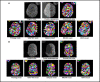

Segmenting three-dimensional (3D) microscopy images is essential for understanding phenomena like morphogenesis, cell division, cellular growth, and genetic expression patterns. Recently, deep learning (DL) pipelines have been developed, which claim to provide high accuracy segmentation of cellular images and are increasingly considered as the state of the art for image segmentation problems. However, it remains difficult to define their relative performances as the concurrent diversity and lack of uniform evaluation strategies makes it difficult to know how their results compare. In this paper, we first made an inventory of the available DL methods for 3D cell segmentation. We next implemented and quantitatively compared a number of representative DL pipelines, alongside a highly efficient non-DL method named MARS. The DL methods were trained on a common dataset of 3D cellular confocal microscopy images. Their segmentation accuracies were also tested in the presence of different image artifacts. A specific method for segmentation quality evaluation was adopted, which isolates segmentation errors due to under- or oversegmentation. This is complemented with a 3D visualization strategy for interactive exploration of segmentation quality. Our analysis shows that the DL pipelines have different levels of accuracy. Two of them, which are end-to-end 3D and were originally designed for cell boundary detection, show high performance and offer clear advantages in terms of adaptability to new data.